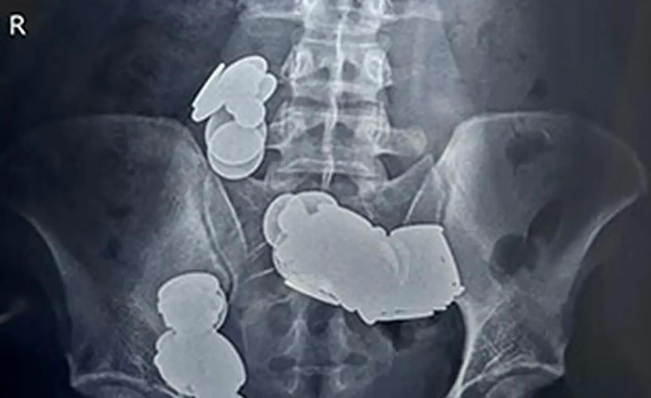

Slika članka

Imate to krvno skupino? Strokovnjaki opozarjajo da je povezana z nastankom sladkorne bolezni

Ta krvna skupina je povezana z nekoliko večjim tveganjem za razvoj sladkorne bolezni tipa 2, vendar strokovnjaki poudarjajo, da ima življenjski slog še vedno ključno vlogo.